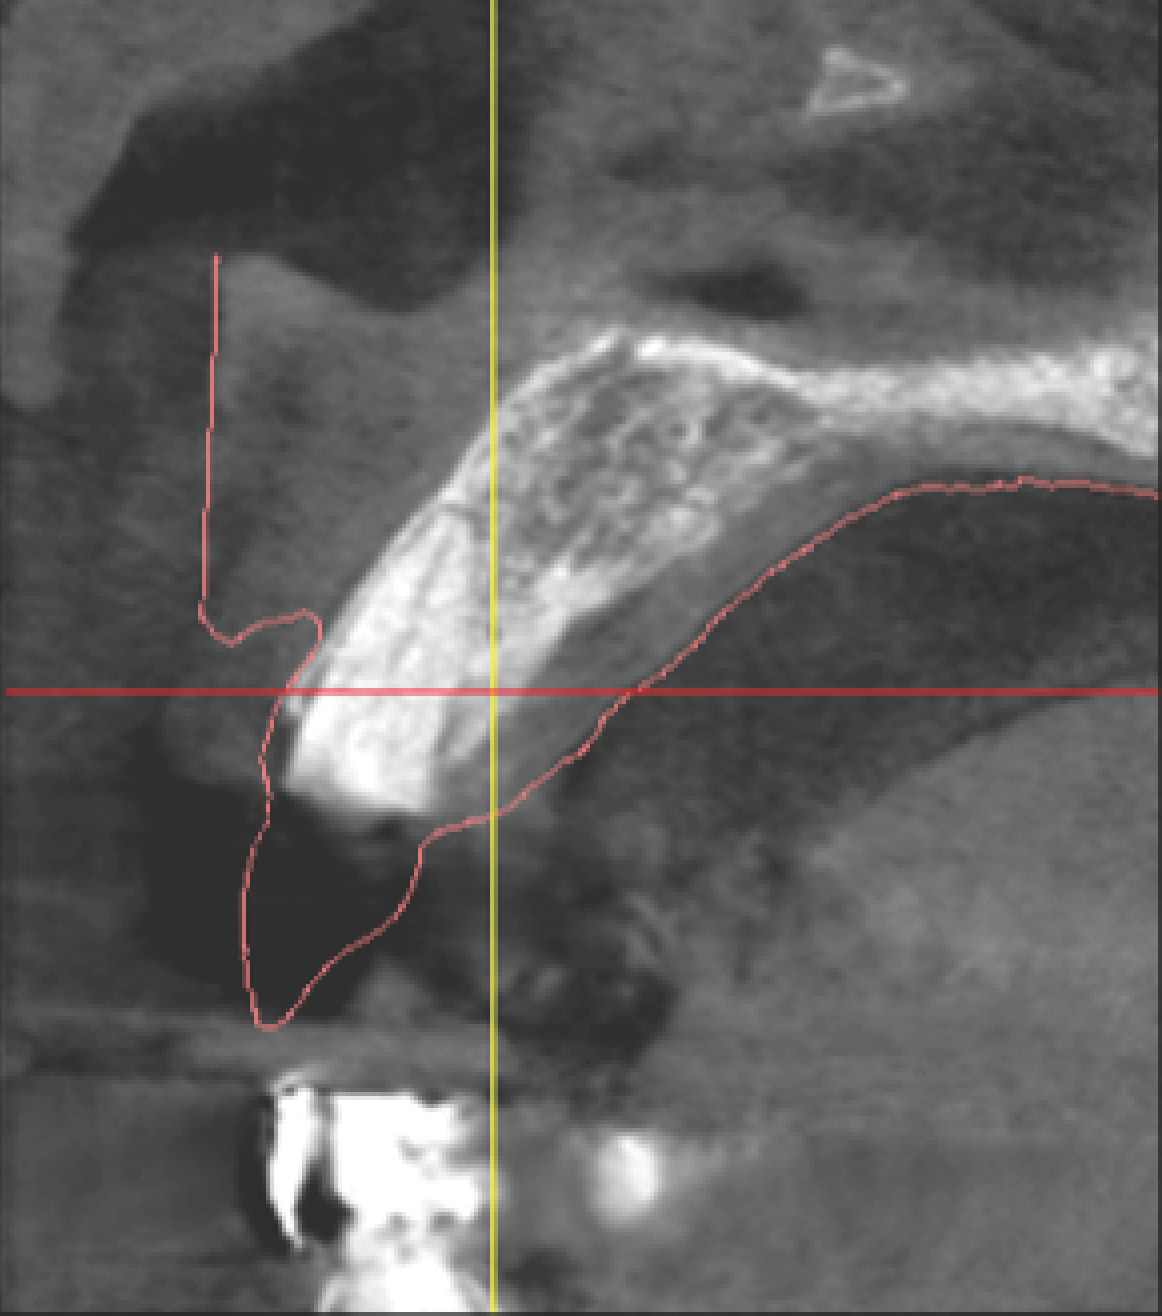

With all of this needed information relative to the pre-operative condition and proposed final tooth position, the treatment moved into the assessment and planning phase. The CBCT revealed an intact buccal plate anterior to the root of tooth No. 8 with adequate bone surrounding the area in all dimensions. Because of the favorable bony contours, an immediately placed implant was decided upon and planned in the software. The CEJ of the proposed final tooth location was identified and an OsseoSpeed EV 4.2 C - 11 mm implant (Dentsply Implants) was planned 3 mm apical and 2 mm lingual to that landmark12 to assure adequate biologic and prosthetic space for the final restoration (Figure 3 through Figure 5). A Simplant SAFE Guide was selected and ordered to convey all of the positional parameters of the final implant position, including depth control and implant timing.

Fig 3 through Fig 5. The Simplant plan of the future implant position 3 mm apical and 2 mm

lingual to the CEJ of the proposed final restoration, including final guide design.